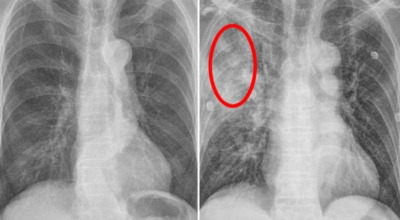

폐암 검사는 주로 X-ray를 통해 이루어지지만, 종양의 크기가 작거나 구석에 위치한 경우에는 확인이 어려운 경우도 있습니다. 그 후, 조직 검사를 통해 정확한 진단을 하게 됩니다. 폐암이 발견되면, 종양의 크기, 전이 여부, 위치에 따라 수술 여부를 결정하게 됩니다.